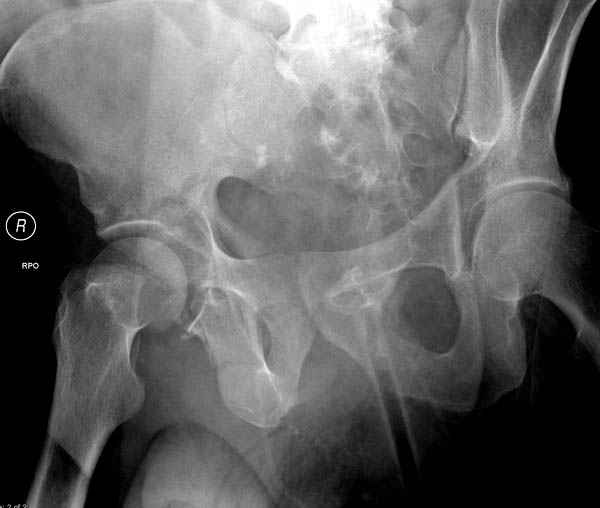

По возможности вышлите снимки, сканы таза до

реконструкции, интраоперационные.

По снимку создается впечатление о высоком поперечном переломе, задней колонны, стенки; почему не пользовались *magic screw*?

Снимки здесь....